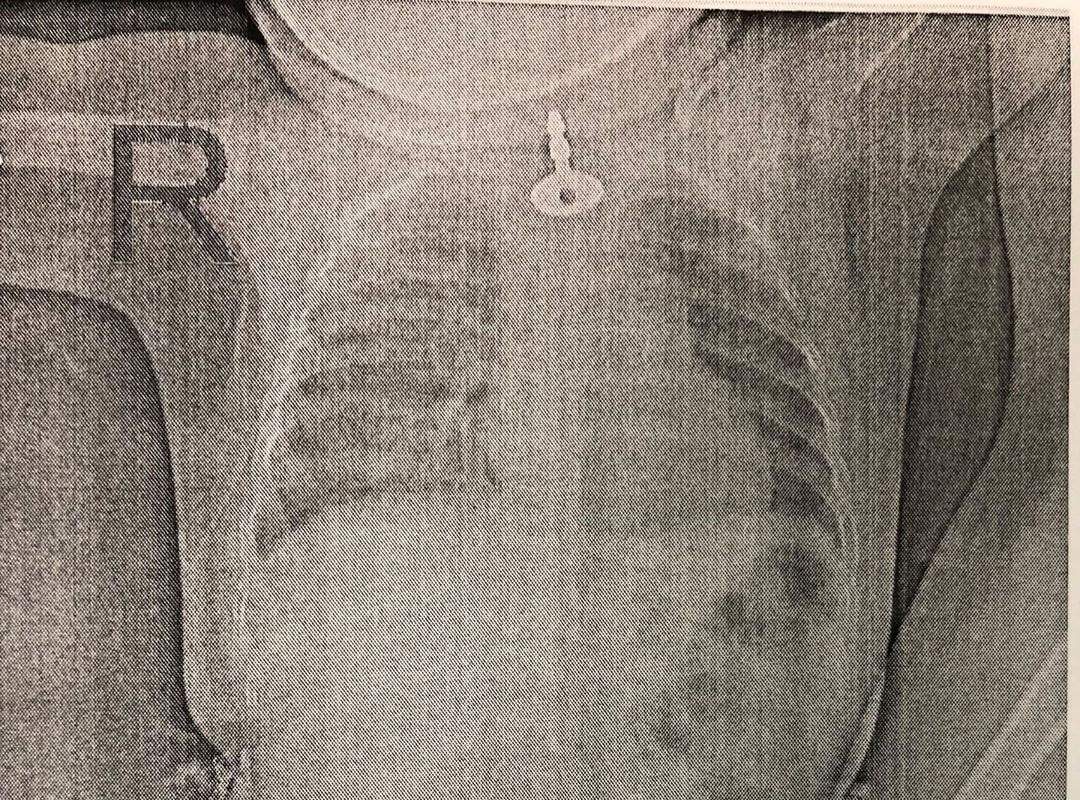

Ребенок проглотил крестик

Ребенок проглотил крестик 108 фотографий